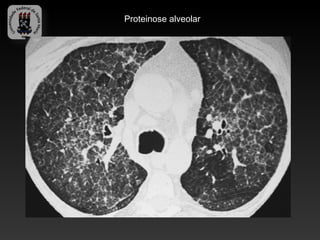

-PROTEINOSE ALVEOLAR PULMONAR

-Caracterizado por acúmulo de material fosfolipoproteico, derivado de

surfactante nos espaços alveolares.

-Pode ser adquirida, congênita ou secundária a outras condições

-Radiografia pode mostrar padrão em “borboleta”

-Achados da TC:

-   Pavimentação mosaico.

Proteinose alveolar